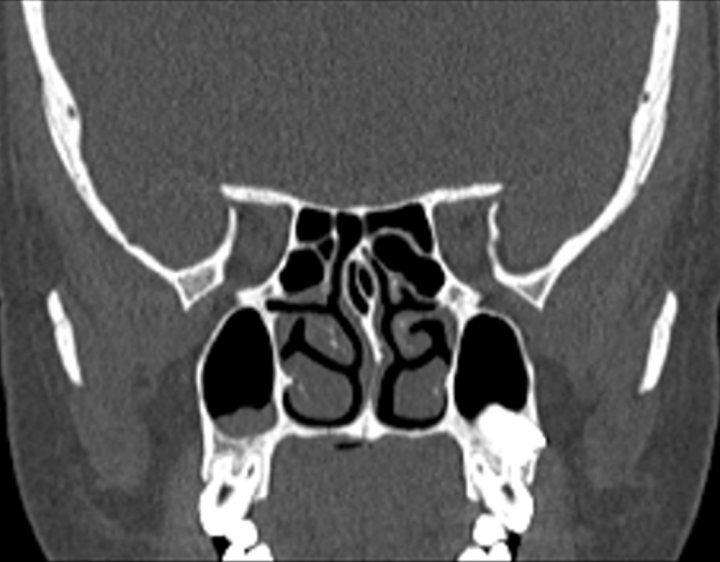

002